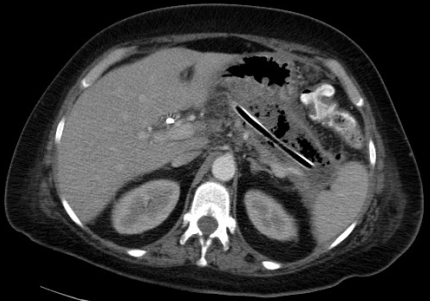

Early operative intervention in patients with pancreatic necrosis is now reserved for very select cases in which specific criteria for operation are met, including concern for concomitant intra-abdominal catastrophe or rapid and life-threatening clinical deterioration despite maximal medical care (2). In the absence of these criteria, patients with necrotizing pancreatitis should be initially managed with aggressive, supportive medical care, maximizing cardiopulmonary and nutritional support. Numerous studies support continuing this supportive approach for at least 4 weeks after disease onset to allow acute peripancreatic fluid collections to resolve or mature into the more chronic phase of walled-off necrosis3,4. Any patient with necrotizing pancreatitis that has a clinical deterioration at any time, such as a new fever or leukocytosis, warrants aggressive workup for infected necrosis. Findings indicative of infection include a positive Gram stain or culture on fine needle aspiration (FNA) of the pancreatic collection or retroperitoneal gas on contrast-enhanced computed tomography (CT) scan. Fine needle aspiration can be repeated at weekly intervals if clinically indicated, with high sensitivity and specificity and low risk for superinfection5. Once an infection is diagnosed, percutaneous drainage catheter placement is performed with the help of interventional radiology (Figure 1).

Once a percutaneous drain has been placed, aggressive upsizing to 18- to 20-Fr catheters is performed every 3 to 4 days. A CT is repeated 10 to 14 days later. If the patient has a remaining large collection and a minimum of 4 weeks have elapsed since onset of disease, plans are made for a VARD. If not already present, a percutaneous drain should be placed as close as possible to the left costal margin at the midaxillary line (Figure 2).

This drain will be used as a digital guide to access the collection in the operating room (OR). A CT scan should be repeated after this drain is in place. The CT image will serve as a guide for the surgeon in the OR to identify the correct path into the abscess cavity. These are crucial steps that are absolutely necessary for a successful VARD procedure. Two additional steps include having an open laparotomy set and 4 units of cross-matched blood available in the OR. Although bleeding complications are exceedingly rare, there is potential for significant blood loss if they do occur.